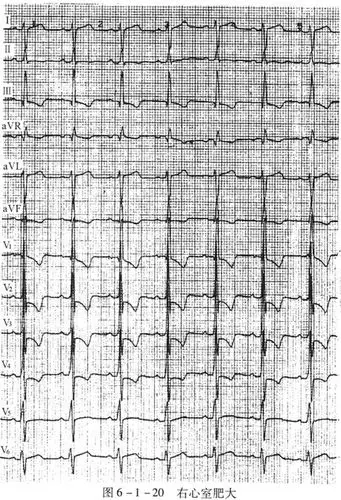

左,右心室肥厚检查 - 问答库